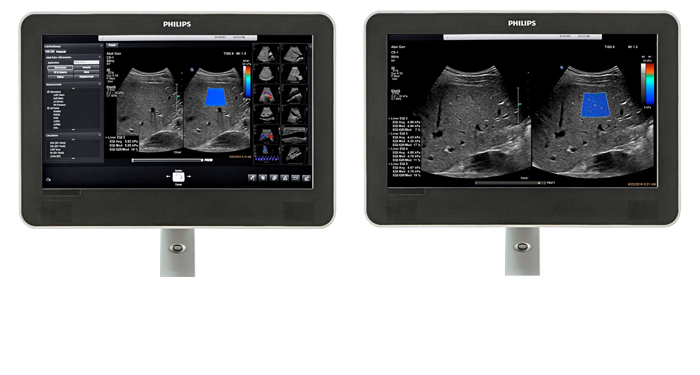

At the touch of a button, the new MaxVue high-definition display brings extraordinary visualisation of anatomy with 1,179,648 additional image pixels compared to a standard 4:3 display format mode. MaxVue enhances ultrasound viewing during interventional procedures and provides 38% more viewing area to optimise the display of dual, side/side, biplane, and scrolling imaging modes.

MaxVue offers a 38% greater viewing area.

MaxVue offers high definition display at the touch of a button.

MaxVue offers 1,179,648 additional image pixels compared to a standard 4:3 display format mode.